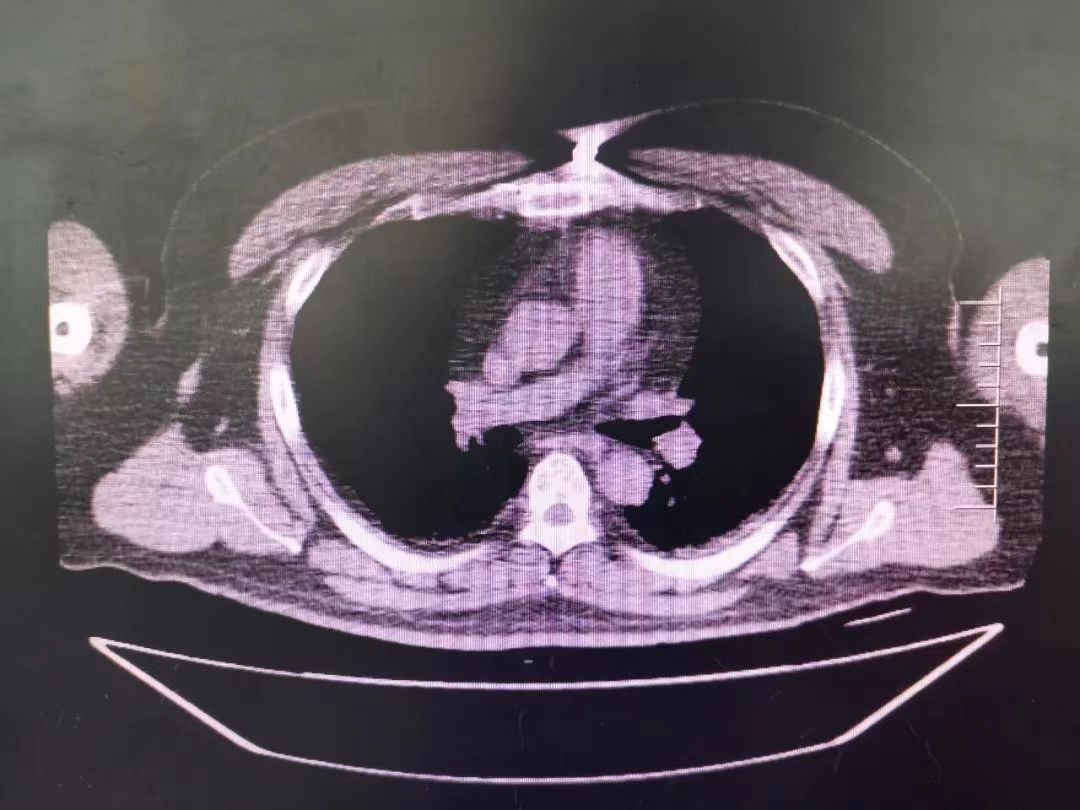

CT室門口,焦燥的家屬不停的走動(dòng)著、等待著,看到醫(yī)生的到來,快速跑到醫(yī)生面前說:“醫(yī)生,快幫我看看,病人怎么樣”。陳醫(yī)生過去一看,一個(gè)體型偏胖的患者平躺在床上,一把剪刀齊根直插胸口觸目驚心,陳醫(yī)生不由眉頭一緊,轉(zhuǎn)身去看電腦CT影像 --剪刀斜著刺入胸骨,將胸骨完全穿透,刀尖距離心包約1-2mm,正下方是主動(dòng)脈,大量心包積液?再一看,患者肥胖,脂肪組織多,不排除脂肪偽影。考慮患者血壓相對平穩(wěn),由于緊張導(dǎo)致心率快,立刻安撫患者,讓其保持安靜,盡量避免咳嗽,避免深呼吸和過多運(yùn)動(dòng)。隨即撥通了武小剛主任的電話:“主任,這有一位患者,銳器刺傷不排除已經(jīng)損傷到心臟,病人目前血壓平穩(wěn)”“嚴(yán)密監(jiān)測患者病情變化,準(zhǔn)備急診手術(shù),我馬上到”武主任說。